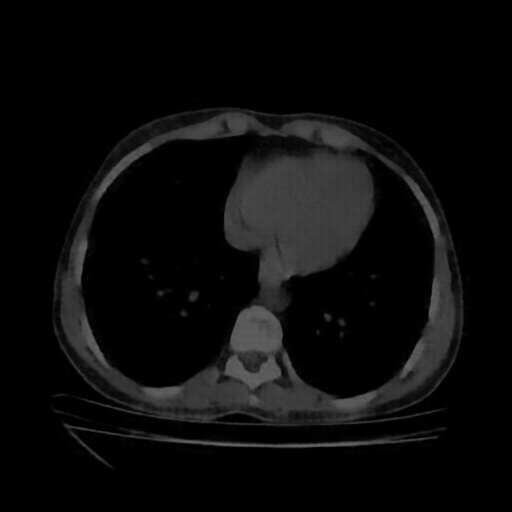

Generated VENOUS CT scan (A→B translation)

No window - Raw intensity values

Lung window (WL -600, WW 1500 β†’ Low βˆ’1350, High +150)

Mediastinum window (WL 40, WW 400 β†’ Low βˆ’160, High +240)